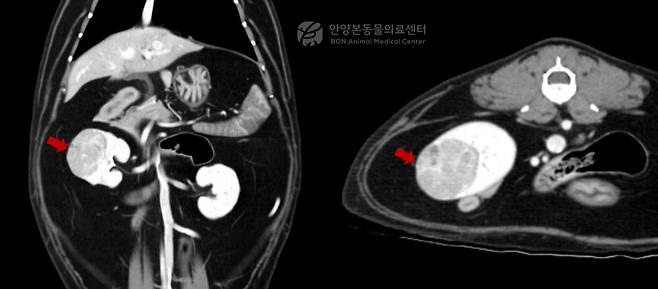

의료진은 수술 전 정밀 평가를 위해 컴퓨터단층촬영(CT)을 실시했다. 검사 결과 우측 신장에 약 2.2×2.2×3.0㎝ 크기의 종괴가 확인됐다. 폐나 복강 내 다른 장기로의 전이 소견은 발견되지 않았다. 이어 초음파 유도 세침검사를 통해 악성 종양인 신세포암이 의심된다는 결과를 얻었다.

이에 따라 의료진은 종양이 한쪽 신장에 국한돼 있고 반대쪽 신장 기능이 정상인 점을 고려해 복강경 신장절제술을 시행하기로 결정했다.